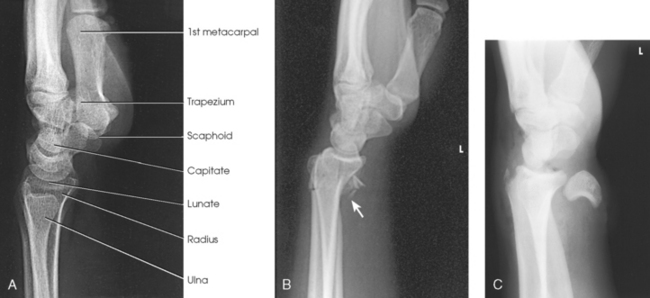

• Carpals: Bones of the wrist (Fig. 4-1)

Five metacarpals, which are cylindric in shape and slightly concave anteriorly, form the palm of the hand (see Fig. 4-1). They are long bones consisting of a body and two articular ends—the head distally and the base proximally. The area below the head is the neck where fractures often occur. The first metacarpal contains two small sesamoid bones on its palmar aspect below the neck (see Fig. 4-1). A single sesamoid is often seen at this same level on the second metacarpal. The metacarpal heads, commonly known as the knuckles, are visible on the dorsal hand in flexion. The metacarpals are also numbered 1 to 5, beginning from the lateral side of the hand.

The wrist has eight carpal bones, which are fitted closely together and arranged in two horizontal rows (see Fig. 4-1). The carpals are classified as short bones and are composed largely of cancellous tissue with an outer layer of compact bony tissue. These bones, with one exception, have two or three names; this atlas uses the preferred terms (see box). The proximal row of carpals, which is nearest the forearm, contains the scaphoid, lunate, triquetrum, and pisiform. The distal row includes the trapezium, trapezoid, capitate, and hamate.

Each carpal contains identifying characteristics. Beginning at the proximal row of carpals on the lateral side, the scaphoid, the largest bone in the proximal carpal row, has a tubercle on the anterior and lateral aspect for muscle attachment and is palpable near the base of the thumb. The lunate articulates with the radius proximally and is easy to recognize because of its crescent shape. The triquetrum is roughly pyramidal and articulates anteriorly with the hamate. The pisiform is a pea-shaped bone situated anterior to the triquetrum and is easily palpated.

Beginning at the distal row of carpals on the lateral side, the trapezium has a tubercle and groove on the anterior surface. The tubercles of the trapezium and scaphoid constitute the lateral margin of the carpal groove. The trapezoid has a smaller surface anteriorly than posteriorly. The capitate articulates with the base of the third metacarpal and is the largest and most centrally located carpal. The wedge-shaped hamate exhibits the prominent hook of hamate, which is located on the anterior surface. The hamate and the pisiform form the medial margin of the carpal groove.

The forearm contains two bones that lie parallel to each other—the radius and ulna. Similar to other long bones, they have a body and two articular extremities. The radius is located on the lateral side of the forearm, and the ulna is located on the medial side (Figs. 4-4 and 4-5).